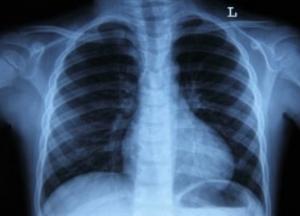

Рак легких – самое распространенное злокачественное образование в мире, которое характеризуется скрытым течением и ранним появлением метастазов. Первым признаком заболевания считается затяжной кашель. Также на начальных стадиях происходит потеря аппетита, появляются слабость и усталость.